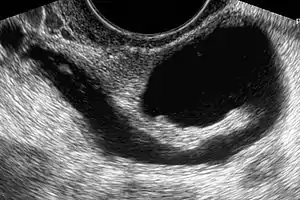

Sonohysterography. The sterile saline instilled into the cavity of the uterus is anechoic (rendered as dark in the middle of the image). It shows a normal endometrium as a hyperechoid (brighter) band around the cavity, in this case without any focal changes.

Sonohysterography is a specialized procedure by which fluid, usually sterile saline (then called saline infusion sonography or SIS), is instilled into the uterine cavity, and gynecologic sonography performed at the same time. A review in 2015 came to the conclusion that SIS is highly sensitive in the detection of intrauterine abnormalities in subfertile women, comparable to hysteroscopy. SIS is highly sensitive and specific test in the diagnosis of uterine polyps, submucous uterine fibroids, uterine anomalies and intrauterine adhesions (as part of Asherman's syndrome), and can be used as a screening tool for subfertile women prior to IVF treatment.[4]

Sonohysterography using a balloon catheter (seen in the middle of the image)